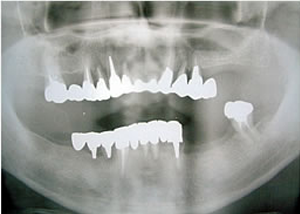

5.終了時レントゲン

治療完了

平成19年5月1日

(治療期間:2年10ヶ月)